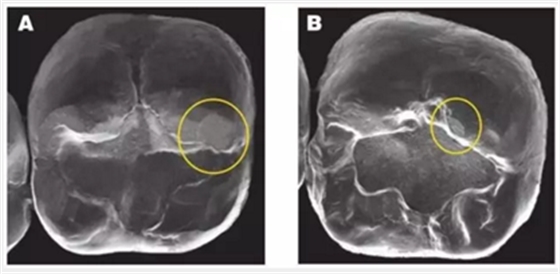

2. 牙冠對(duì)對(duì)頜牙造成的磨損:這三種冠材料與對(duì)頜牙的接觸中都會(huì)造成小的磨損平面(加下圖)BruxZir 的磨損平面更大也更多。這些修復(fù)體使用一年后出現(xiàn)的磨損平面,需要更多的時(shí)間去觀察。(見(jiàn)下圖)

圖像A和圖像B 顯示了Bruxzir和切削類e.maxCAD全冠對(duì)對(duì)頜牙造成的磨損平面。本次研究中所有的材料(包括控制對(duì)照組)都會(huì)一些造成類似的小磨損平面。無(wú)論對(duì)頜牙是釉質(zhì)、鑄造金屬、復(fù)合樹(shù)脂還是瓷。